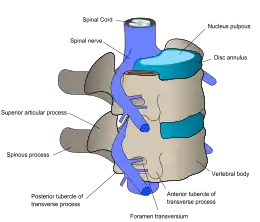

![]() | |

| Спинальні нерви виходять зі спинного мозку між кожною парою хребців. | |

На рівні кожного хребця спинномозкові нерви відгалужуються з обох боків спинного мозку і виходять між парою хребців, щоб іннервувати (обслуговувати) конкретну частину тіла. Ділянка шкіри, іннервована специфічним спинальним нервом, називається дерматомом, а група м'язів, іннервована одним спінальним нервом, називається міотомом. Частина спинного мозку, яка була пошкоджена, відповідає спинним нервам цього рівня й нижче.